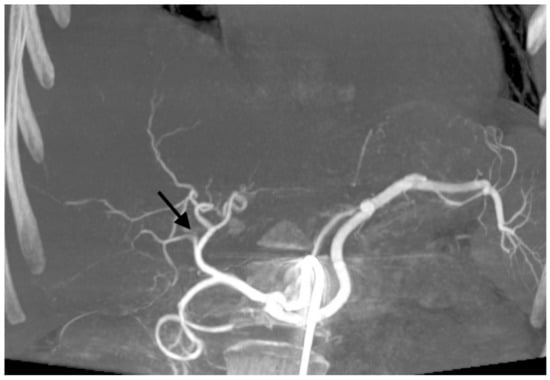

With 192 chemoembolizations, 14 (7.3%) serious complications were found. The most complications were found with the administration of embolizate at the level of the lobar arteries. There was no significant correlation between the branch level of embolization and the presence of complications (chi-squared = 2.9331, df = 2, p-value = 0.2307; Table 5). In two cases, an anaphylactic reaction occurred with moderate hypotension, skin redness, and coughing occurring during the procedure; this resolved after the intervention of the anesthetic team. Two other patients with severe and prolonged pain in the right upper quadrant showed signs of cholecystitis (without bilirubin increase) in ultrasound, which resolved after conservative treatment. In another two patients, features of liver decompensation with ascites were found. One patient experienced a septic episode with liver abscess 2 weeks after the last treatment, which was successfully treated by antibiotic therapy. Follow-up imaging studies showed signs of dilatation of the bile ducts in two patients as a result of damage, (Figure 1). Two patients had occlusion of the right or left branch of the hepatic artery (Figure 2). Three patients, 21 days after surgery, had leukopenia <2000 mm3, requiring the date of the next transcatheter arterial chemoembolization (TACE) session to be shifted by an additional week or two. There were no deaths in the periprocedural period or within 30 days of the procedure.

Figure 2. Cone-beam computed tomography showing occlusion of the right branch of hepatic artery (black arrow) after transarterial chemoembolization with drug-eluting microspheres preloaded with irinotecan.